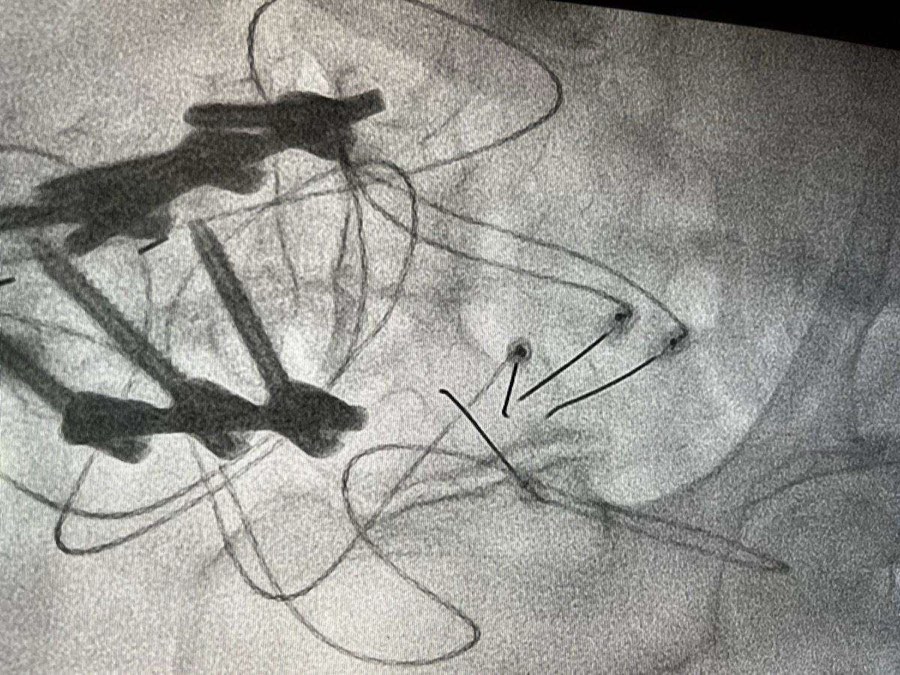

During lumbar facet injections, the patient is positioned on the tummy ( prone position) and the skin overlying the targeted facet joints is sterilized. Under fluoroscopic guidance, a needle is precisely advanced to the target facet joint, and a combination of local anesthetic and steroid medication is injected. This aims to provide both diagnostic information and therapeutic relief by reducing inflammation and blocking pain signals.

For patients who experience significant but temporary relief from facet joint injections, RFA may be recommended. This procedure involves using specialized radiofrequency needles to selectively heat and ablate the nerves responsible for transmitting pain signals from the facet joints. We carefully target the medial branches of the dorsal rami , the nerves responsible for causing back pain , under fluoroscopic guidance to disrupt pain transmission while preserving other sensory functions.